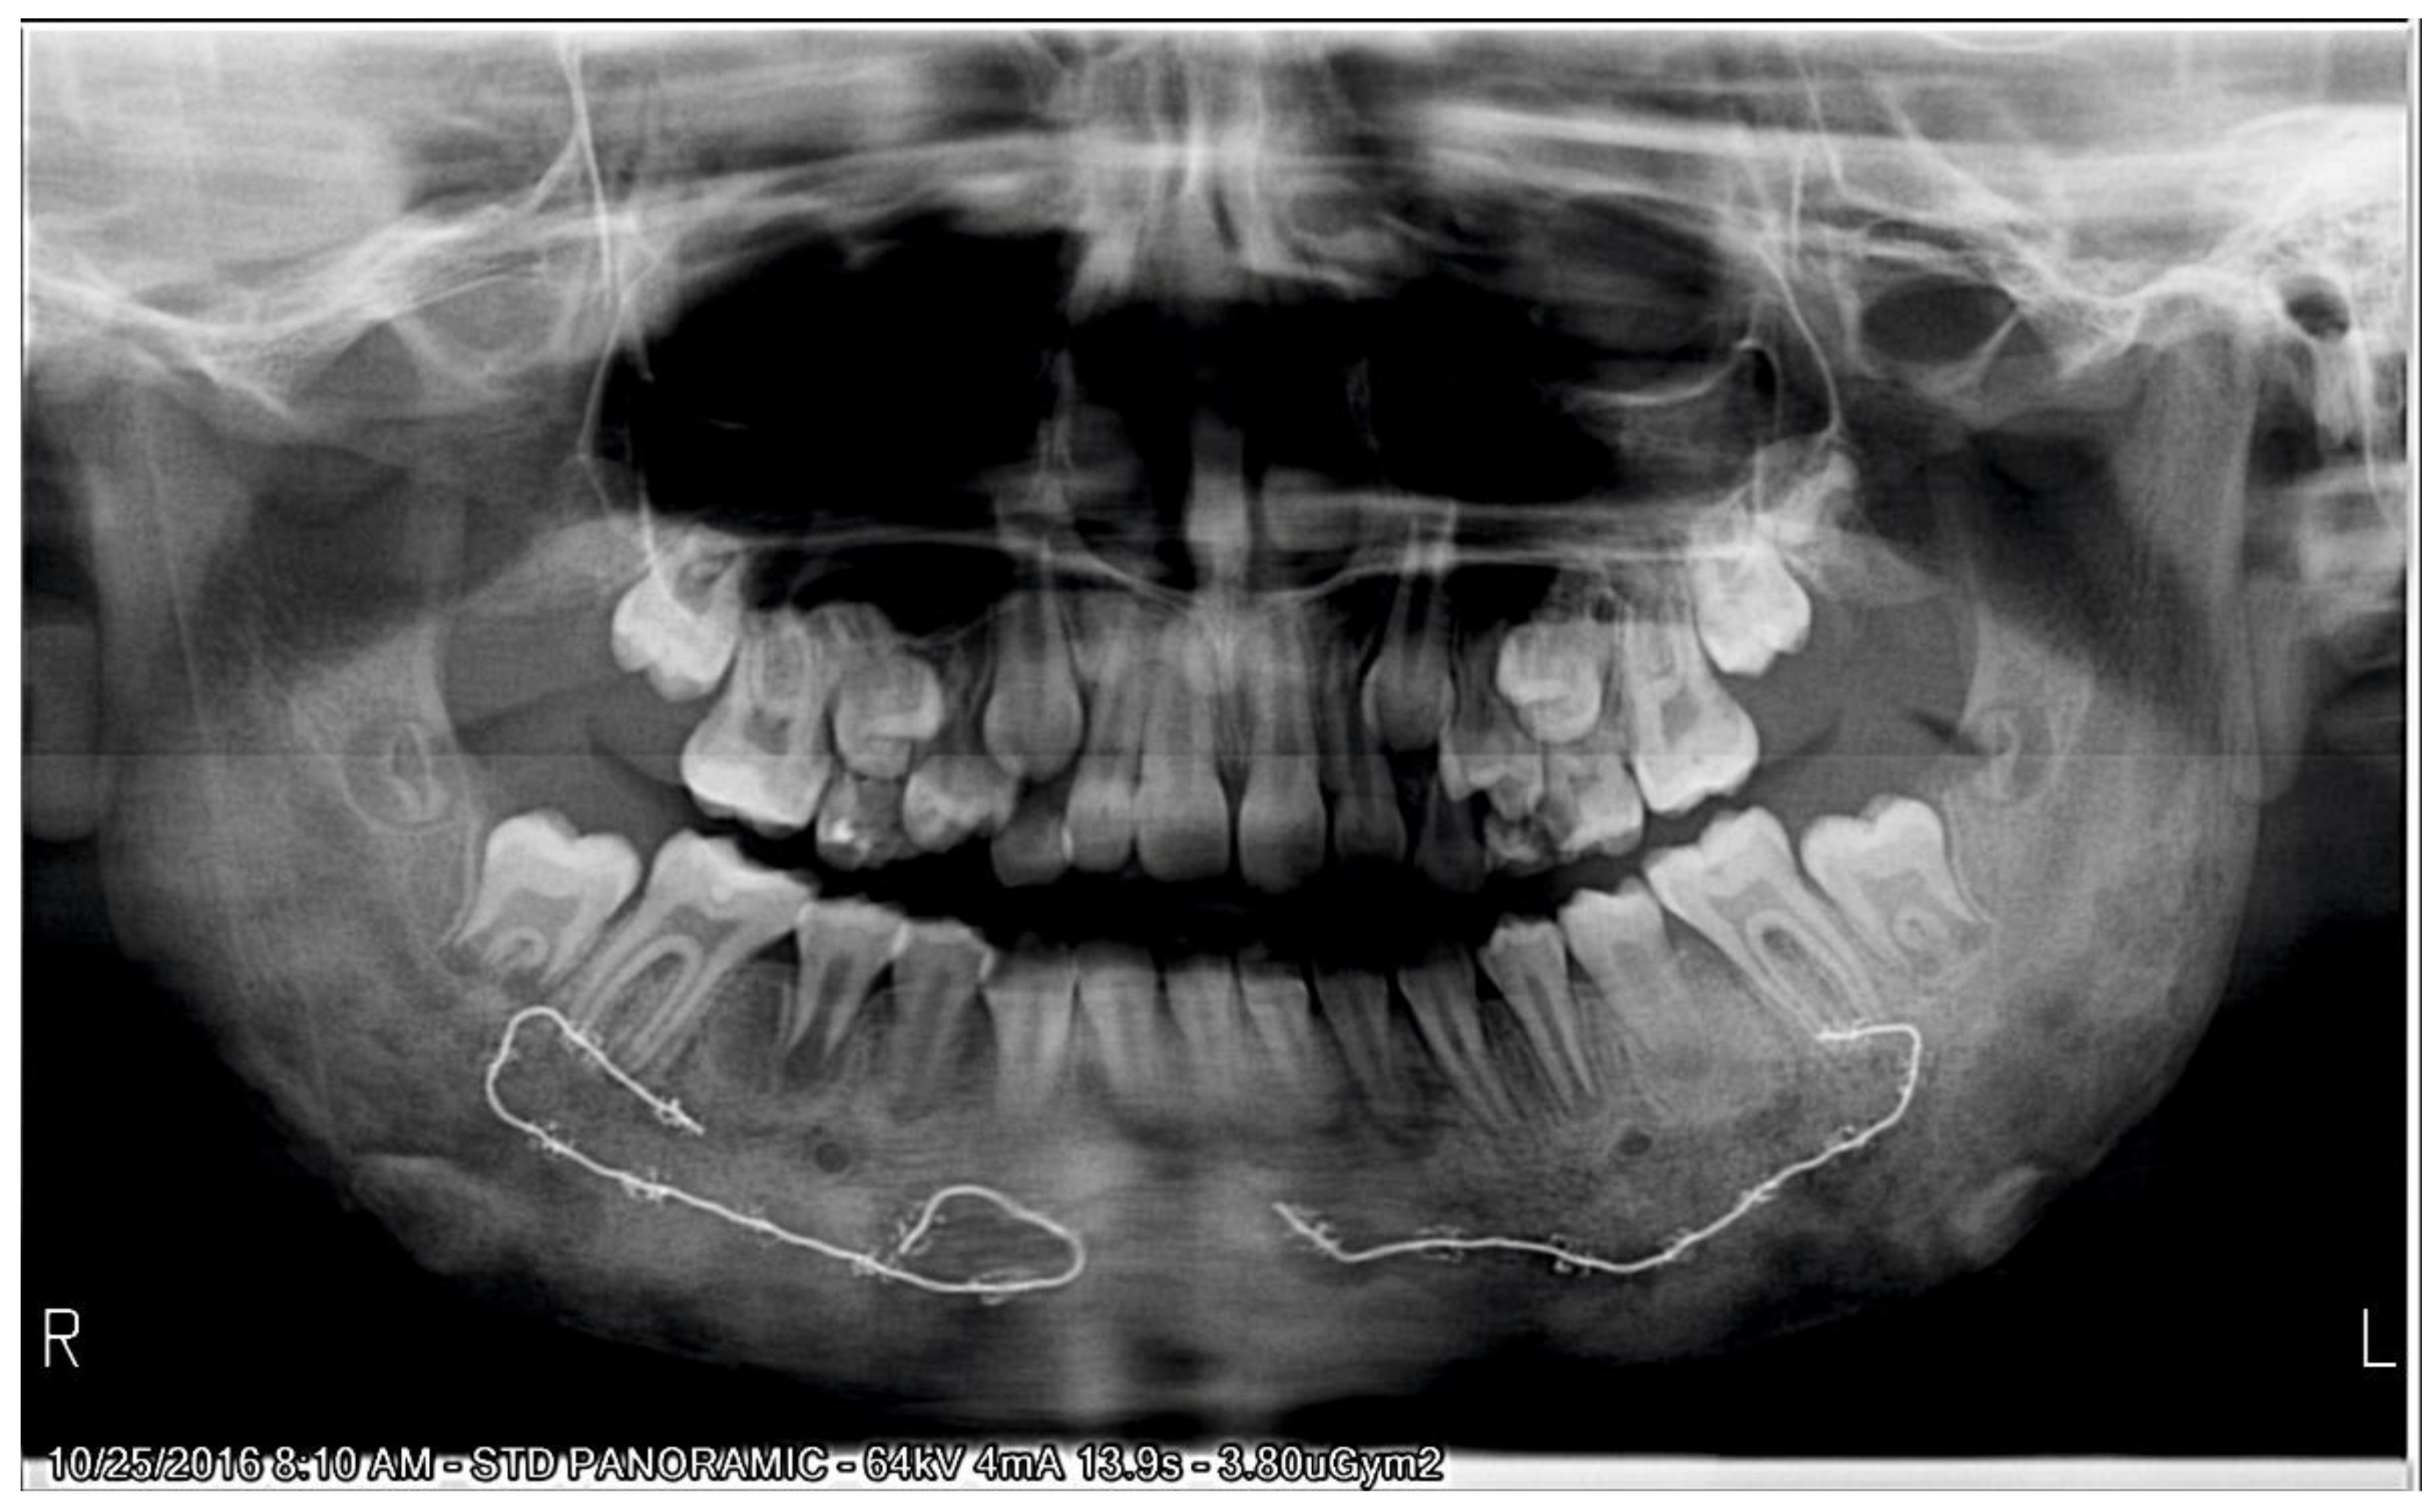

2.1. Initial Diagnosis and Initial Surgical Management

2.2.1. Initial Examination